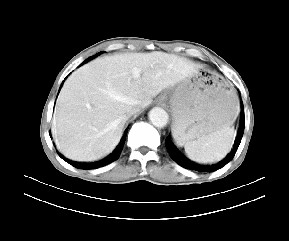

标题: CT19533:病变来源于哪?

患者,男,发现上腹部包块两月余。

病变位于肝胃间隙,实际就是位于小网膜囊(左肝下后间隙),呈轻度不均匀性强化,腹腔内及腹膜后见多发肿大淋巴结。所以我考虑肝胃间隙恶性胃肠间质瘤并淋巴结转移。

病灶强化不显著,灶周及腹膜后见多量淋巴结肿大,考虑淋巴瘤可能,其次考虑间质瘤

病灶与胰腺分界不清,来源于胰腺?

强化后病变与胃壁分界清楚,并且血供不是来源胃壁血管。考虑胰腺颈体癌并腹腔腹膜后淋巴结转移。